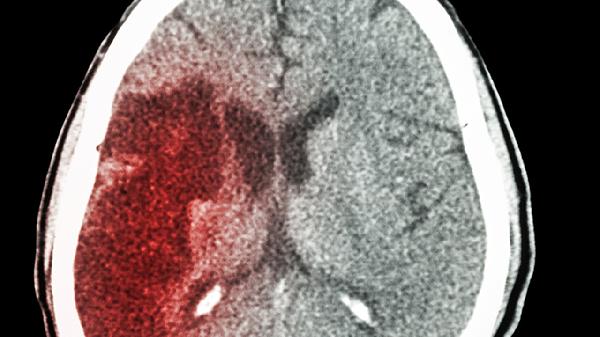

婴幼儿脑出血后遗症主要包括运动障碍、认知发育迟缓、语言障碍、癫痫发作及视觉听觉异常。脑出血后遗症与出血部位、出血量及治疗时机密切相关,需通过早期康复干预改善预后。

脑实质出血后皮质瘢痕可能成为致痫灶,约三成患儿会出现局灶性发作。可遵医嘱使用左乙拉西坦口服溶液控制发作,定期监测脑电图。家长需记录发作形式与持续时间,避免患儿单独沐浴或游泳,发作时保持侧卧位防止窒息。